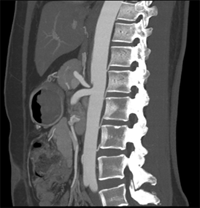

目前臨床對于16層CT的認可主要集中在三維成像領域上的突破.在16層CT的產品平臺上,常規(guī)掃描就能實現(xiàn)滿足三維成像的要求,因此16層也被稱為三維CT,三維成像給臨床診斷帶來了更精確更豐富的診斷信息,我們以臨床為例:

如上圖所示,相鄰的三張軸位圖像未見明顯異常,根據(jù)傳統(tǒng)軸位圖像很難得到準確的臨床診斷。

同一病人利用容積數(shù)據(jù)進行三維處理后,高品質MPR和三維圖像上則清晰顯示了縱向排列的腹腔干與腸系膜上動脈相鄰近,血管發(fā)生變 異,近端血管閉塞,為臨床提供了精確的診斷信息。

從上面的例子可以看到,能否為臨床提供高品質的三維影像成為了16層CT的核心價值,而東芝新一代的 全景三維16層CT擁有最為  先進的3項核心技術,在16層核心價值上的表現(xiàn)自然值得期待。